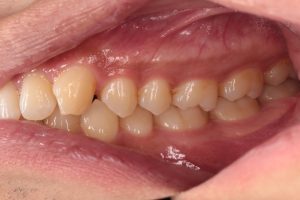

左の写真は上下の歯がかみ合っていない状態、右の写真は上下の歯がかみ合っている状態

右の写真のようにかみ合っているのが正常ですが、中心結節の突起が折れてしまいやすいので早めの処置が必要です。